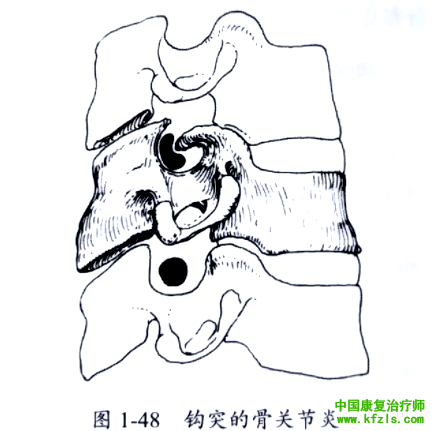

颈椎钩突为C3~C7椎体上部两侧向上的嵴状突起。钩突增加椎体的稳定性,并构成椎间孔的前内侧界(图1-47)。钩突骨质增生时可累及椎间孔,直接压迫神经根或限制神经根的活动(图1-48)。

但当发生车祸时,由于头部和颈部剧烈伸展或弯曲可导致继发的神经根反应性水肿,使得本已狭窄的椎间孔压迫神经根。狭窄的椎间孔常如图1-48所示,这种结构使创伤后水肿的神经根失去活动空问而导致疼痛。疼痛和上肢的神经系统査体通常即可明确受累神经根。

如创伤引起的C6神经根损伤可导致前臂外侧的感觉减退,伸腕肌肌无力和肱桡肌反射消失(图1-40)。但也可出现唯一症状:肩胛骨的内上角和内侧缘疼痛。

活动的范围越大,受伤的几率也越大,,骨关节炎导致的钩突骨质增生常发生在C5~C6水平。